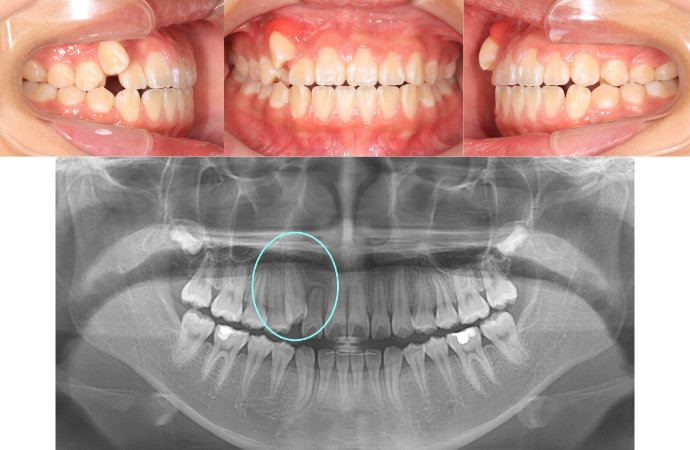

| Case3 |

| 受け口 |

| <治療前> |

|

| <治療後> |

| 主訴 |

上の歯がねじれている |

| 診断名 |

叢生を伴う反対咬合 |

| 年齢 |

10歳 |

| 使用装置 |

マルチブラケット装置 |

| 抜歯部位 |

永久歯の抜歯は無し |

| 治療期間 |

3年6か月 |

| 治療費概算 |

検査・診断料:5万円+税 装置・技術料:25万円+税 おおよそ1か月ごとの処置・管理料:5,000円+税 保定装置料:5万円+税 |

| リスク・副作用 |

う蝕 |